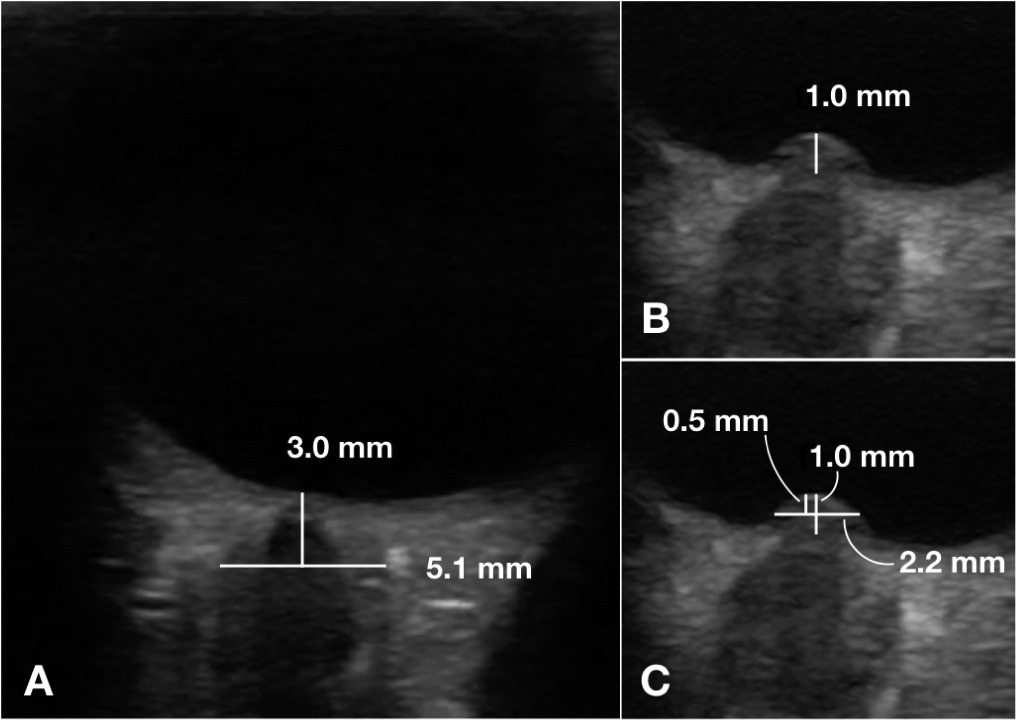

The Optic Disc Elevation #ODE for ⇡ICP study we have all been waiting for is here! https://t.co/RnSsVOnyYm ✱ 76 pediatric eyes ✱ ODE AUC .962 vs ONSD .778 ✱ Best cut off 0.66mm ⇢ Sens 96%, Spec 93% HT @doctorlianne. Nice work @PEMPOCUS et al!